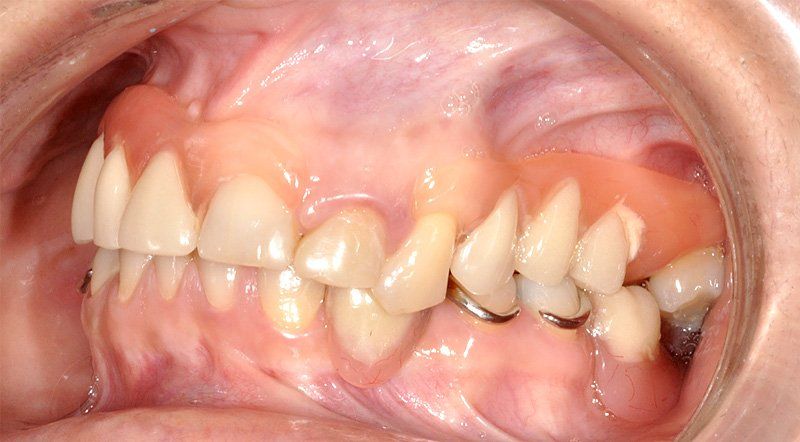

Los Implantes de Carga Inmediata son una solución práctica y definitiva para el desdentado total, es un tratamiento el cual una vez que se opera y se colocan los implantes, por un periodo entre 24 horas a 48 horas, se colocan los dientes en forma provisional, de esta forma el paciente queda con algo fijo mientras el implante se adhiere al hueso. Su principal ventaja radica en la reducción o eliminación del tiempo de espera entre la colocación del implante dental y la colocación de los dientes fijos.

Porque se hace en pabellones certificados por la Universidad de Chile. Son dependencias hechas única y exclusivamente para hacer intervención en sitios estériles. También se hace más cómodo y se pasa rápido el periodo de espera. Del momento en que se insertan los implantes debe transcurrir un período de tiempo de entre 4 a 6 meses si es en mandíbula o maxilar superiores respectivamente para que el tejido óseo cicatrice y logre integrarse a la superficie del implante